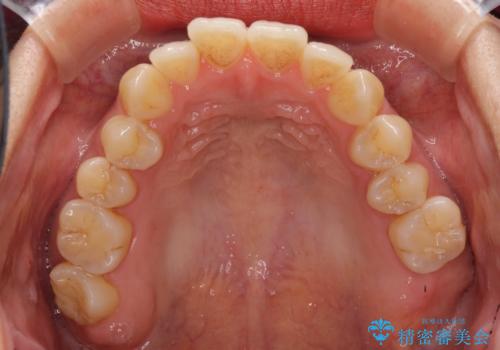

前歯のデコボコ インビザラインによる矯正治療

- 上下前歯の叢生と奥歯の反対咬合を気にして来院された患者様です。

インビザラインを用い、下顎はIPR(歯と歯の間を削る)と歯列全体を後方に移動させ、上顎は側方に拡大させることで歯列を改善していくこととしました。

骨格的に下顎が左側前方にずれているため、上下正中のズレや左右奥歯の咬み合わせを理想的な状態とすることは困難でした。